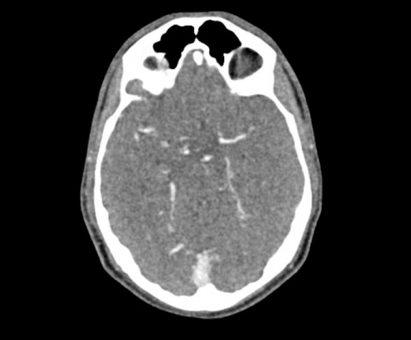

El maniquí de cabeza proporciona una simulación extremadamente realista de una angiografía por TC de cabeza y cuello (con contraste arterial) de un paciente con una malformación arteriovenosa en el lado derecho. El maniquí se entrega fiel a la escala original e incluye la columna cervical hasta la placa base de la quinta vértebra cervical.

Este fantasma se crea a partir de datos de pacientes reales y se fabrica con la última tecnología. Los huesos, vasos y tejidos blandos se muestran auténticamente con valores de TC realistas para todos los tejidos a un voltaje de tubo de 120 kVp en el TC. Si el maniquí se va a utilizar principalmente con otros voltajes de tubo (por ejemplo, 100 kVp), la calibración de los valores de CT se puede ajustar en consecuencia si es necesario. El fantasma proporciona contrastes de tejido realistas en las imágenes de rayos X. Los espacios aéreos se llenan con un material con aproximadamente -80 unidades Hounsfield.